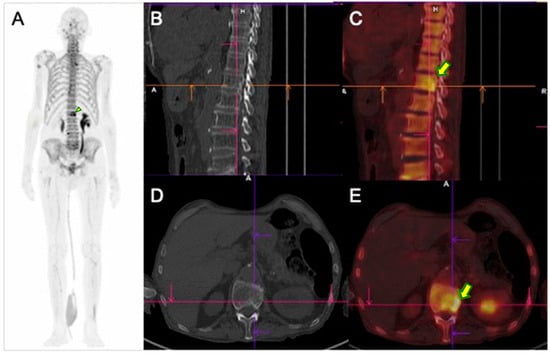

3.1. Diagnosis with Bone Scintigraphy (SPECT/CT) with 99mTc-MDP

3.2. Diagnosis with PET/CT with 18F-Fluoride